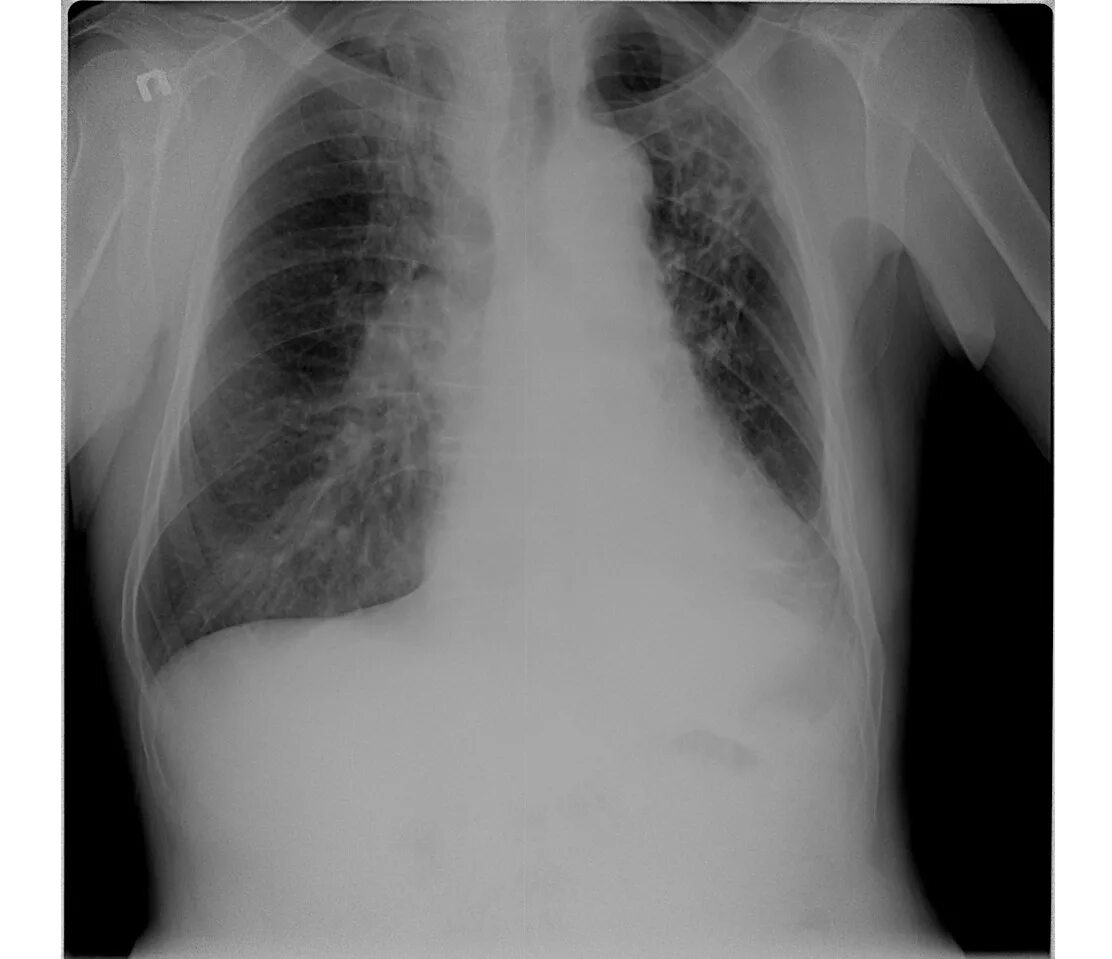

Фиброзное изменение левого легкого